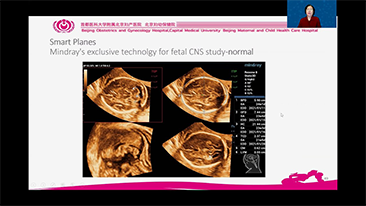

Optimierte OBG-Workflows sind n?tig, wenn gro?e Patientinnenzahlen im Rahmen von Gesundheitsscreenings bew?ltigt werden sollen. Zum Beispiel sind Fehlbildungen des zentralen Nervensystems (ZNS) eine der h?ufigsten angeborenen Anomalien. Wegen verschiedener f├╝r die Bildgebung ung├╝nstiger Bedingungen, etwa eine schwierige Position des F?tus, ist es besonders schwer, die MSP von 2D-Ultraschall zu erhalten. Aus diesem Grund k?nnen automatisierte Erkennung und Messungen die Scanning-Effizienz deutlich steigern.